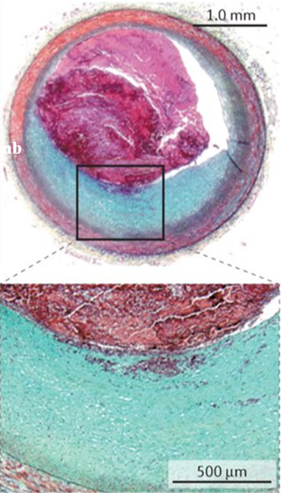

Olika typer av plack

Stabilt plack med fibrös kapsel kan vi leva med. Denna har bara enstaka T-celler och monocyter.

Vad är det som gör att den fibrösa kapseln blir tunn och bindvävsfattig hos instabilt plack?

Vad kännetecknar fenotypiskt det instabila placket?